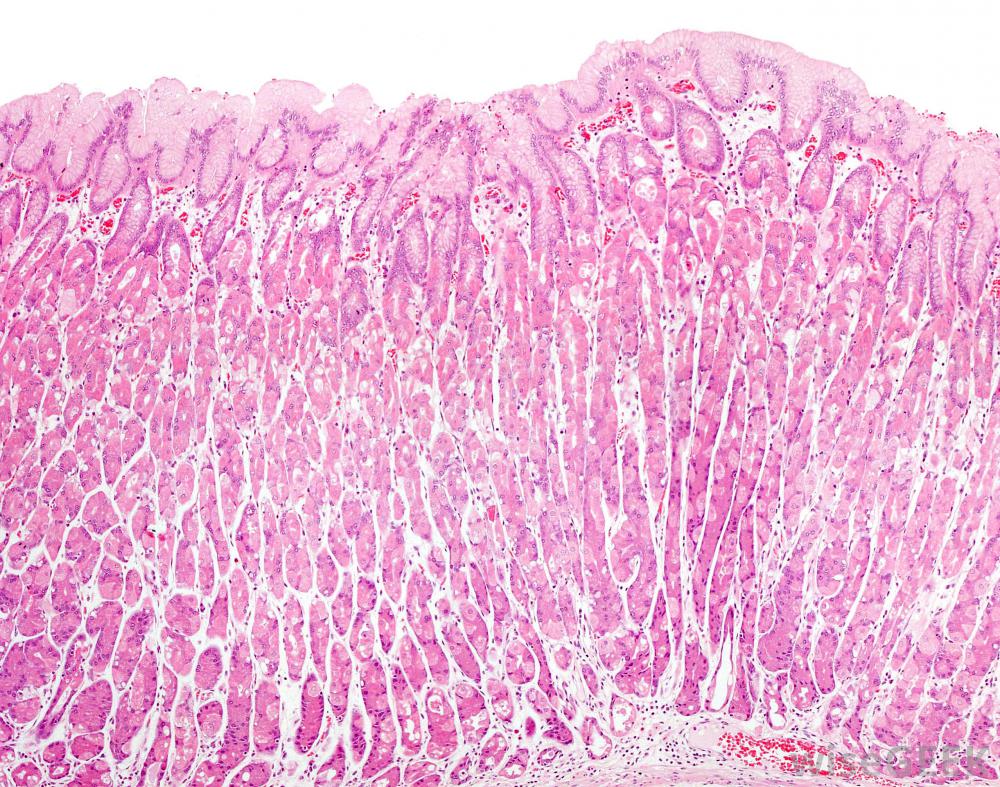

胃壁细胞产生粘液,保护胃免受酸侵蚀粘液也是人体最丰富的润滑剂。当颗粒在呼吸过程中被截留后,身体通过称为纤毛的细小移动的毛发将润滑的物质推向胃。在胃中,酸可以完成杀死任何可能感染健康细胞的病原体的过程。消化系统中的细胞也会产生大量的粘液,这些粘液被用作润滑剂,帮助食物通过食道。胃的内壁也需要一层润滑剂,因为酸性物质虽然有助于杀死感染性微粒,但如果没有得到充分的保护,它也会吞噬形成内膜的细胞。女性生殖系统依靠粘液来帮助调节其周期。在排卵期间,产生的物质清澈流淌,水性润滑剂有利于精子的接收和受精,排卵后,它变得更厚,这种物质还含有更多的抗生素蛋白质,可以阻止精子从阴道走得更远,阻止受精:男性生殖系统通过精囊与精液结合产生精子,这种粘液含有碳水化合物和糖类,在精子生命周期中为精子提供营养。